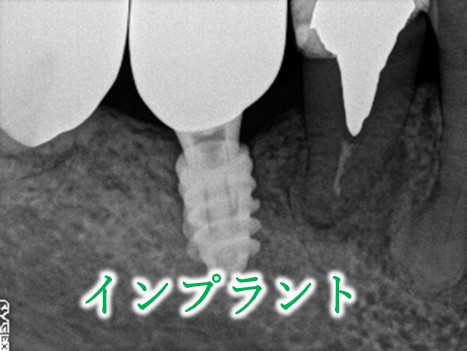

治療内容

ブリッジの支台になっている奥の歯が、被せ物の中で虫歯になり、支台の役割を果たさず、前方の歯のみで支えられていました。前方の歯をそのままにして、後方の部分を切り離すと、そのまま取れてきました。中は、虫歯で歯根しか残っていない状況でした。この歯は、根管治療後、単独でオールセラミック冠を被せ、歯のないところにインプラントを埋入しました。

所感

今回の治療法には、次の3つの方法があります。

(1)虫歯になっていた歯の根管治療をし、土台を入れ、また再びブリッジにする。しかし、虫歯になっていたほうの歯は、ブリッジの支台として使うには、心もとなく長持ちしない可能性が高く、今度問題が生じたときには抜歯になる。

(2)虫歯になっていた歯に、単独で被せ物をし、歯のないところに1本だけの部分入れ歯を入れる。取り外しの入れ歯なので、自分の歯のような感覚で噛むことはできない。この方法も歯のない部分の負担を欠損の両側の歯に負担してもらうため、長持ちしない可能性が高い。

(3)虫歯になっていた歯に、単独で被せ物をし、歯のないところにインプラントを埋入する。欠損している部分の負担を前後の歯に負担させないので、歯を守ることができる。また、自分の歯と同じ感覚で食事をすることができる。

患者さんは、3つ目の方法を選択されました。一番長持ちし、これ以上歯を失わないためには、最良の方法だと考えます。

Before

冠の中で大きな虫歯になり支台の役割を果たしていませんでした。

【インプラント埋入前】

冠はブリッジを切断しただけで取れてきました。軟化象牙質を取り除いたところ、歯根しか残っていない状況で保存できるかどうかのぎりぎりのところでした。